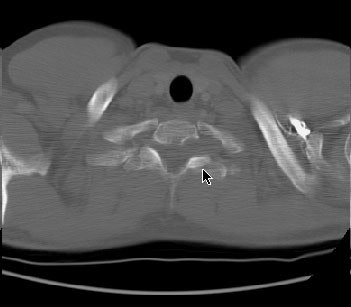

The CT scan revealed a homogeneous low density mass within the left lung apex- on careful evaluation, the mass could be seen extending outside the thoracic cavity and into the T1 neural foramena (middle image on top row and bone window shown below)